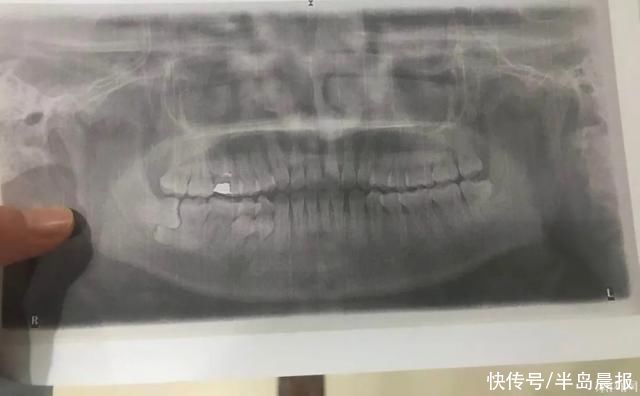

姑娘总共拔了 6 颗牙。2 颗多生牙,4 颗智齿。

11 月 30 号住院,12 月 2 号手术全麻下拔除,4 号出院,10 号拆线。总共花费 7800 多,医保报销 4200 多,历年支付 2000 多,住院预交款 3000,退款 1400。